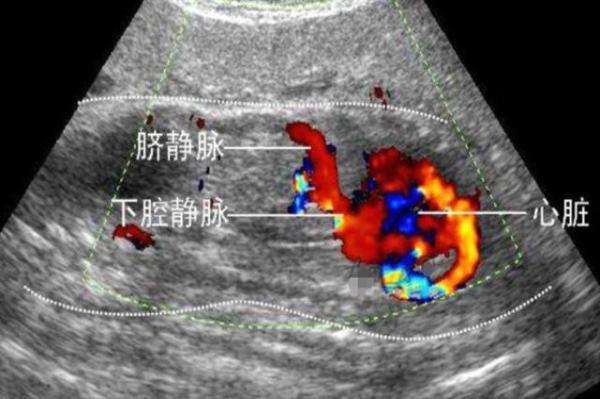

2、排畸B超和普通B超的功能一样,在排除胎儿畸形方面,并没有什么特殊之处。二者主要的区别在于,普通的B超是一张二维的平面照片,而四维彩超则相当于一个立体的录像,父母可以通过看四维彩超看到胎儿在妈妈腹中的活动状况。

3、胎儿的内脏B超能够看到的畸形是非常严重的结构畸形才能看出来,并且,看到的只是当时胎儿的状况。而像阿丽这样,在B超的时候能看到两个肾,但是在后期却发生了融合,那就无法预测到了。